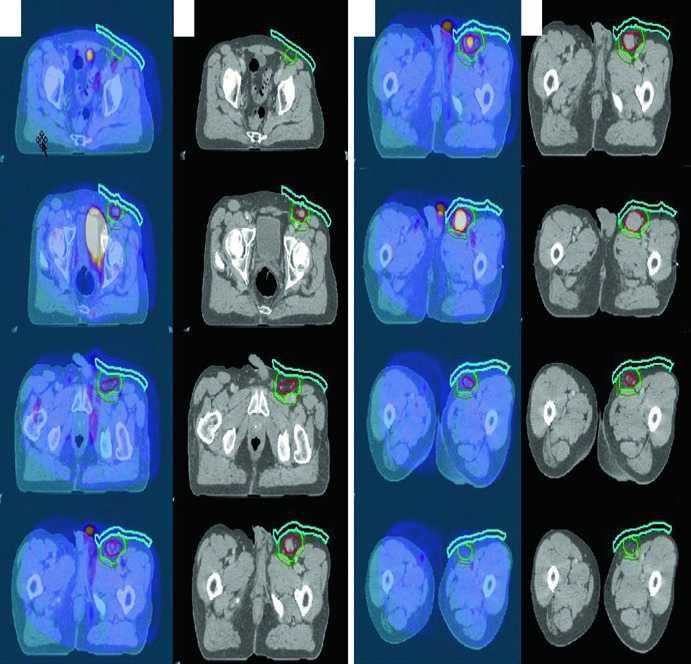

Linfoma Folicular Inguinal

Um homem de 70 anos com linfoma folicular grau I/II estádio IA da região inguinal/femoral esquerda foi tratado com RT definitiva isolada. O PET diagnóstico foi fusionado à CT de simulação. Bolus foi usado para aumentar a dose superficial e melhorar a cobertura dosimétrica — detalhe frequentemente esquecido em lesões subcutâneas inguinais.

Linfoma Inguinal e Pélvico

A simulação deve ser feita em posição de “pernas de rã” para separar a coxa da genitália externa e aplainar pregas cutâneas inguinais, minimizando reações de pele. Em homens, blindar os testículos com clamshell e recomendar criopreservação de esperma. Em mulheres em idade reprodutiva, considerar a posição dos ovários. Técnicas modernas como 3DCRT e IMRT são recomendadas, com adição de bolus quando necessário para dose superficial.